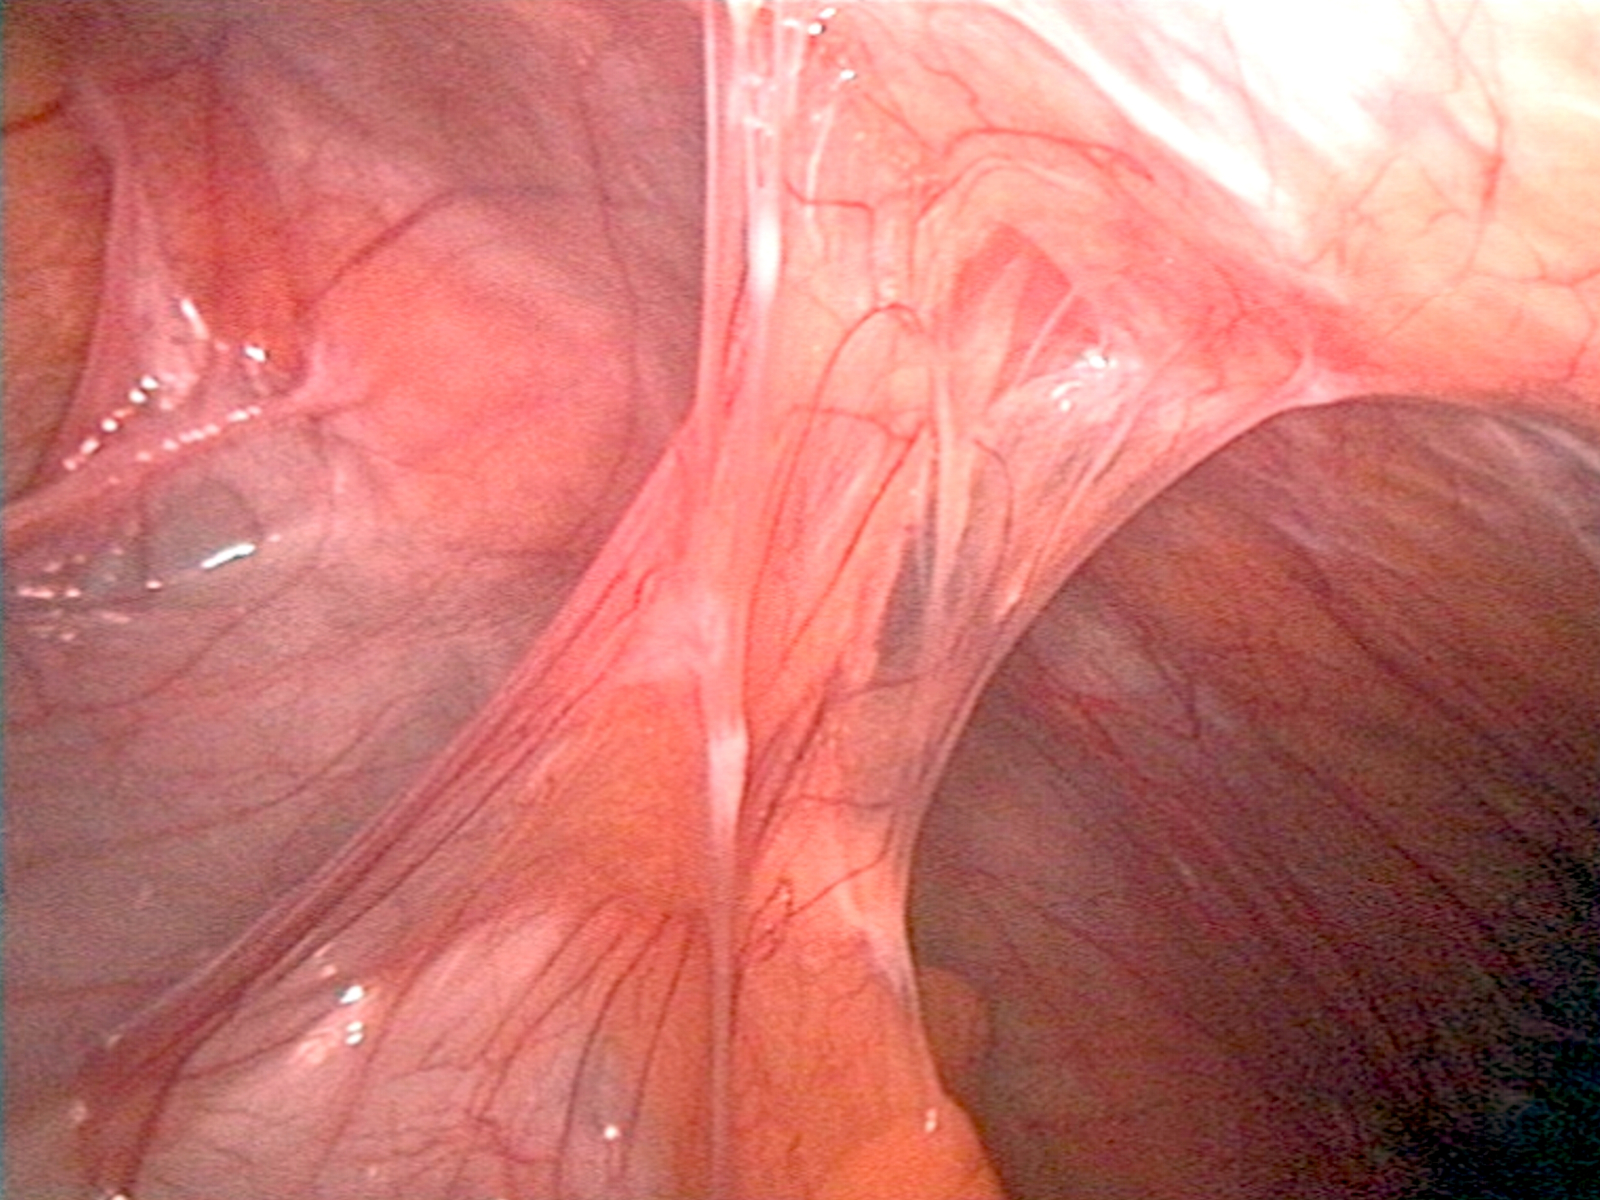

Dans certains contextes post-opératoires en gynécologie, des adhérences peuvent se former. Il s’agit de bandes de tissu fibreux anormal qui se développent entre des organes ou structures internes, souvent en réponse à une inflammation, une infection ou un traumatisme chirurgical. Ces adhérences sont la première complication tardive après une chirurgie (hystéroscopie ou coelioscopie) et peuvent provoquer douleurs, infertilité, ré-intervention…

Pour prévenir l’apparition de ces adhérences, l’utilisation de barrières anti-adhérence est fortement recommandée. Ces dispositifs médicaux sont appliqués à la fin de l’intervention chirurgicale sur les zones à risque. Leur rôle est de séparer temporairement les surfaces tissulaires durant la phase de cicatrisation, afin de limiter les contacts directs et ainsi réduire le risque d’accolement pathologique.

En gynécologie chirurgicale, l’utilisation d’une barrière anti-adhérence a pour objectif de prévenir la formation d’adhérences post-opératoires. Leur apparition peut avoir des conséquences cliniques importantes : douleurs pelviennes chroniques, troubles menstruels, diminution de la fertilité, voire occlusion tubaire.

Les barrières anti-adhérences se présentent sous différentes formes (gels, films, poudres) et agissent en créant une séparation physique temporaire entre les tissus, le temps que la muqueuse utérine ou le péritoine cicatrise de façon optimale. Elles sont particulièrement indiquées lors de gestes chirurgicaux à risque élevé d’adhérences, tels que la myomectomie (ablation de fibromes), la chirurgie de l’endométriose, la chirurgie tubaire, ou encore certaines hystéroscopies opératoires (comme la résection de synéchies ou de cloisons utérines).